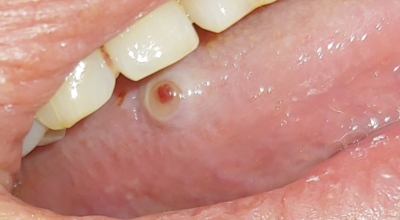

병소는 대부분 혀의 측면이나 밑부분에 발생하며 배면이나 중앙부에는 잘 발생하지 않는데 특히나 측면 중앙부나 후방 1/3에 발생하며 혀끝 쪽 발생은 드문 것으로 알려져 있어요. 암종은 점차적으로 성장하면서 궤양을 형성하고 혀의 움직임이 자유스럽지 못하다 보면서 음식물을 섭취하는데 어려움을 겪게 돼요.

3주 이상이 지나도 낫지 않는 입 안의 궤양

입 안의 궤양이란 입 안 점막이 헐거나 파인 것을 말하는데 보통은 가장 흔한 원인은 아프타 구내염등의 염증 때문이지요. 이런 구내염 때문에 한 군데에 생긴 궤양은 대개 1~2주 내로 없어지지만 심한 경우, 다른 부위에 또 옮겨가기도 합니다. 그러나 한 군데에 생긴 궤양이 3주가 되었는데도 아물지 않는다면 일반적 염증이 아닐 수 있기 때문에 병원을 방문해 보는 것이 좋아요.

구강 점막의 적색 혹은 백색 반점

볼이나 혀에 적색 혹은 백색 반점이 생긴 경우도 대부분은 원인을 잘 모르거나, 만성 자극에 의해서 점막에 변화가 생겨 발생한 일시적인 증상일 가능성이 높아요. 그러나 이런 점막의 변화는 드물게 암의 초기 증상이거나 암으로 변하는 전단계일 수 있어요. 따라서 이전에 진단 받은 적이 없는 경우라면 전문의의 진료를 받는 것이 좋고, 오래된 반점인 경우 최근에 더 두꺼워지거나 헐거나, 범위가 넓어지는 경우, 조직 검사를 받아 보는 것이 좋아요.